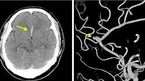

[OSEN=이슈팀] 뇌동맥류 환자가 급증하고 있다. 뇌동맥류 환자가 불과 5년사이에 3.2배나 급중하면서 누리꾼들 사이에서 화제가 되고 있다. 뇌동맥류 환자가 급증한 이유는 추운 날씨와 관련된 가운데 예방법도 동시에 화제다. 뇌